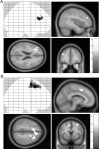

Figure 4.

fMRI results. Greater levels of MT practice predict increased dorsolateral prefrontal (bottom left), right anterior insula (top right), and medial–prefrontal BOLD (bottom right) recruitment during negative emotional processing. Post hoc analysis further revealed this effect to be driven by positive correlations in the MT group. Top left, For visualization purposes, BOLD signal was extracted from the peak voxel (left posterior insula) of this contrast and plotted against practice minutes within MT group. The color bar indicates the t statistic associated with each voxel. A whole-brain statistical parametric map (in yellow) is displayed superimposed on coronal, sagittal, and axial views of the SPM T1-weighted template, for group by time interaction on the negative > neutral contrast. pFWE < 0.05 corrected on cluster level. The voxel selection threshold is p = 0.001.